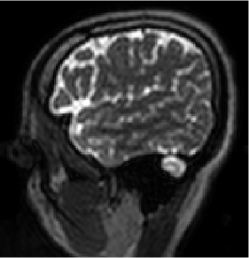

The MRI data used for this study were acquired using a 3D T2 CUBE sequence with Cartesian readouts using a -channel head coil. The matrix dimensions were 256 232 208 with mm isotropic resolution. Fully sampled multi-channel brain images of five volunteers were collected out of which data from four subjects were used for training, while the data from the fifth subject were used for testing. Since the readout is fully sampled, we evaluated the inverse Fourier transform of each readout. We retrospectively undersampled the phase encodes to train and test the framework; we note that this approach is completely consistent with a future prospective acquisition, where a subset of phase encodes can be pre-selected and acquired. All the experiments were performed with variable-density Cartesian random sampling mask with different undersampling factors mentioned at their use.

Figures 7 and 8 visually compare two different slices at 4x and 8x accelerated data acquisition in the presence of Gaussian noise of . The testing slices are from a subject, whose data was not used for training. It is evident from the zoomed portions that the reconstruction quality by the proposed method is better than the techniques compared against.